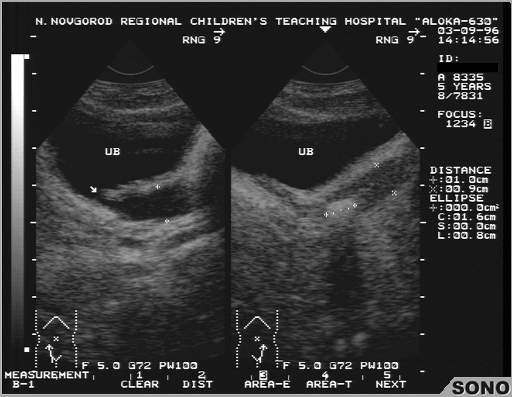

Пациент с энурезом и нейрогенным мочевым пузырем